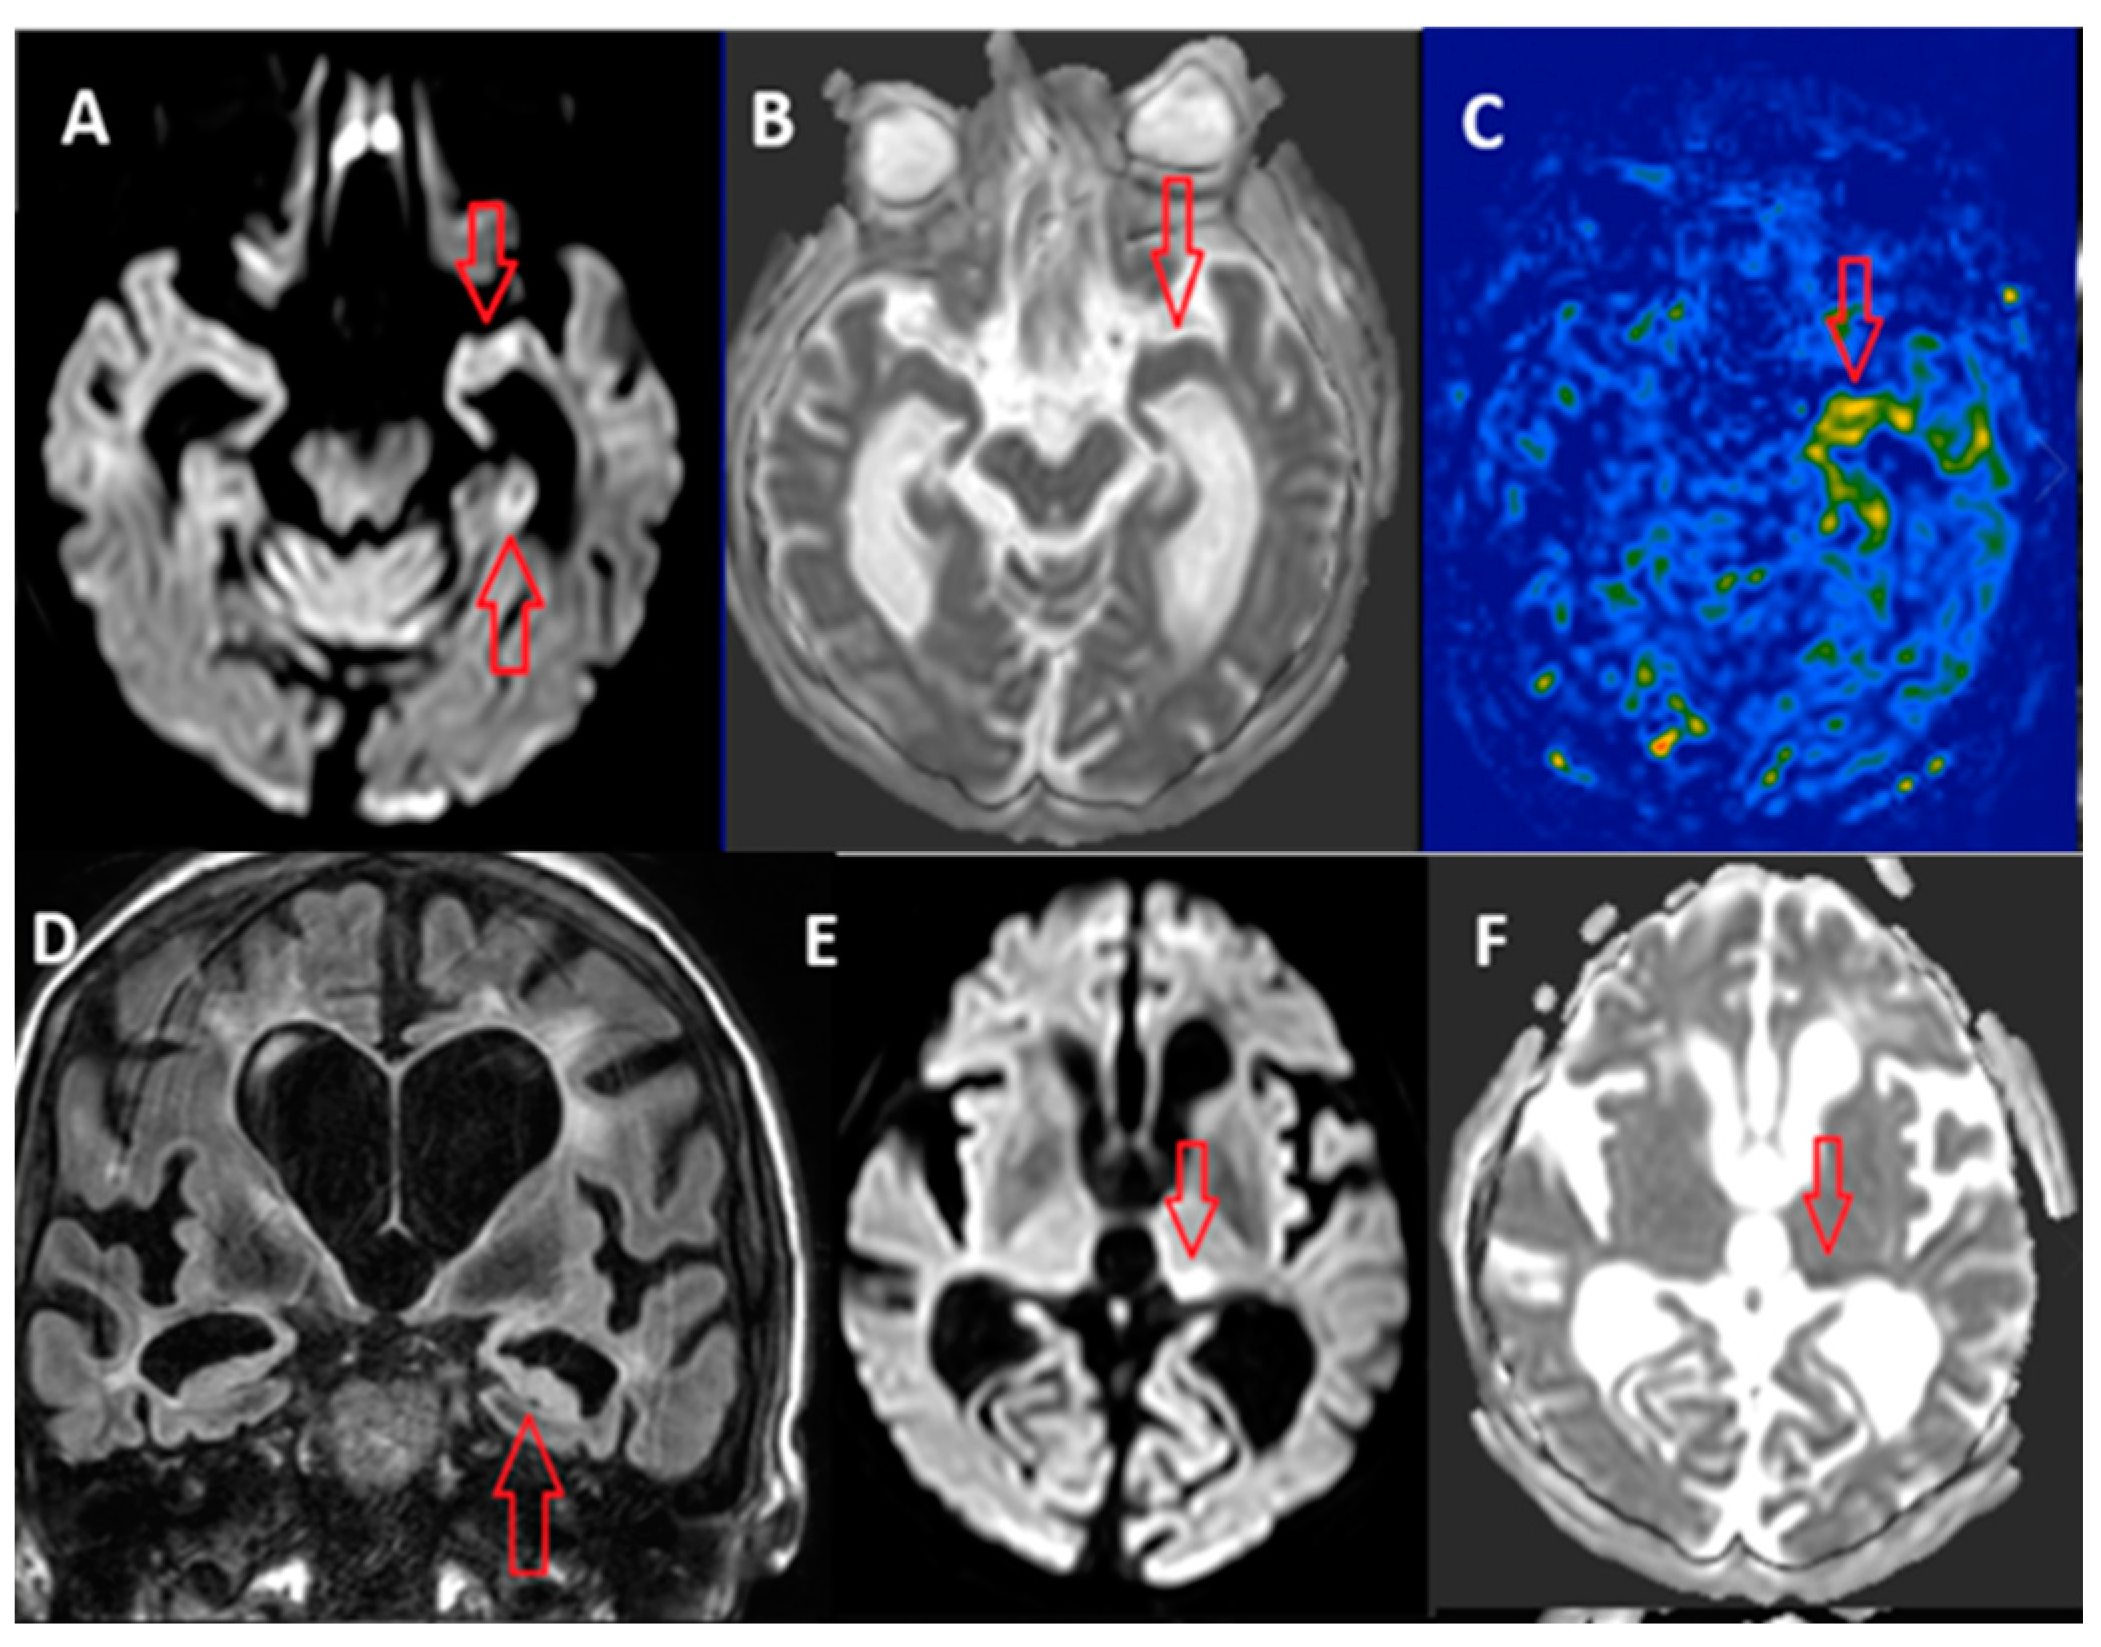

3.1. Arterial Spin Labeling (ASL)

3.2. Susceptibility Weighted Imaging (SWI)